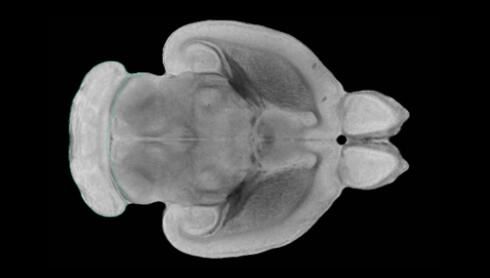

隨著機體年齡增加,肌肉和關(guān)節(jié)都會變得僵硬,這就會使得日常活動變得更加困難,本文研究表明,我們的大腦也是如此,與年齡相關(guān)的大腦僵硬對大腦干細(xì)胞的功能或許有著重要影響。文章中,研究人員對年輕和老化大鼠的大腦進行研究闡明了年齡相關(guān)大腦僵硬對少突膠質(zhì)前體細(xì)胞(OPCs,oligodendrocyte progenitor cells)功能的影響。OPCs是一類對維持正常大腦功能非常重要的大腦干細(xì)胞,其對于髓磷脂的再生也非常重要,髓磷脂是神經(jīng)組織周圍的脂肪鞘,在多發(fā)性硬化癥中髓磷脂的再生常常會被損傷,機體老化對這些細(xì)胞的影響常常會誘發(fā)多發(fā)性硬化癥的發(fā)生,這些細(xì)胞的功能在老化的健康人群中同樣會下降。

為了確定老化OPCs的功能缺失是否可以被逆轉(zhuǎn),研究人員將來自老化大鼠機體的老化OPCs轉(zhuǎn)移到了年輕大鼠柔軟的海綿狀大腦組織中去,值得注意的是,這些老化的大腦細(xì)胞能夠重新恢復(fù)活力,其行為非常像年輕更加強壯的細(xì)胞。這項研究中,研究人員在實驗室中開發(fā)出了具有可變僵硬程度的新型材料,并在受控環(huán)境下研究這些材料的生長及其對大鼠大腦干細(xì)胞的影響,這些材料能被工程化改造具有和年齡或老化大腦相似的柔軟程度。

為了深入理解大腦組織柔軟和僵硬影響細(xì)胞行為的分子機制,研究人員對細(xì)胞表面一種名為Piezo1的蛋白質(zhì)進行了分析,該蛋白質(zhì)能“告知”細(xì)胞其周圍的環(huán)境為柔軟或僵硬。研究者Kevin Chalut說道,我們發(fā)現(xiàn),當(dāng)在僵硬材料上促進年輕具有功能性的大鼠干細(xì)胞時,這些細(xì)胞就會表現(xiàn)出功能異常,并失去其再生的能力,實際上其行為與老化細(xì)胞相似。當(dāng)將老化的大腦細(xì)胞在柔軟材料上生長時,其功能就會表現(xiàn)得像年輕細(xì)胞一樣,換句話說,其能夠重新恢復(fù)年輕的活力。